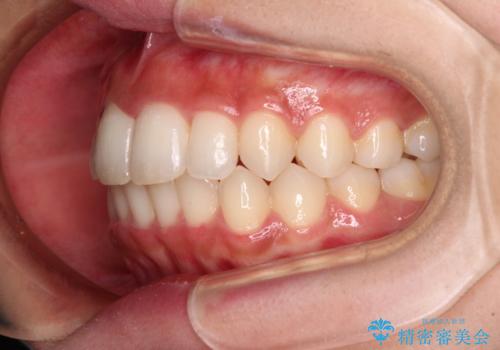

- 上下前歯のデコボコを気にして来院された患者様です。

前歯のセラミックが装着されている歯は、歯根が短くなっており、他院では抜けてしまうので矯正はできないと言われていたようです。

患者様と相談し、抜けてしまった場合にはインプラントあるいはブリッジによる補綴治療が必要となることを確認し、極力歯根に負担のかからないような仕上がりで治療を進めて行くこととしました。

デコボコを解消には、IPR(歯と歯の間を削る)をメインに歯列排列を設計し、インビザラインにて矯正治療を行うこととしました。

レントゲン写真上では、矯正治療前後で歯根長さに大きな違いはなく、抜歯を回避することができました。

上顎内側に転位している前から2番目の歯は移動が難しく、無理矢理歯根全体を動かそうと設計すると、歯肉退縮・歯髄壊死・歯根吸収といった危険性が増すため、無難なゴールにて治療を終えることとなりました。